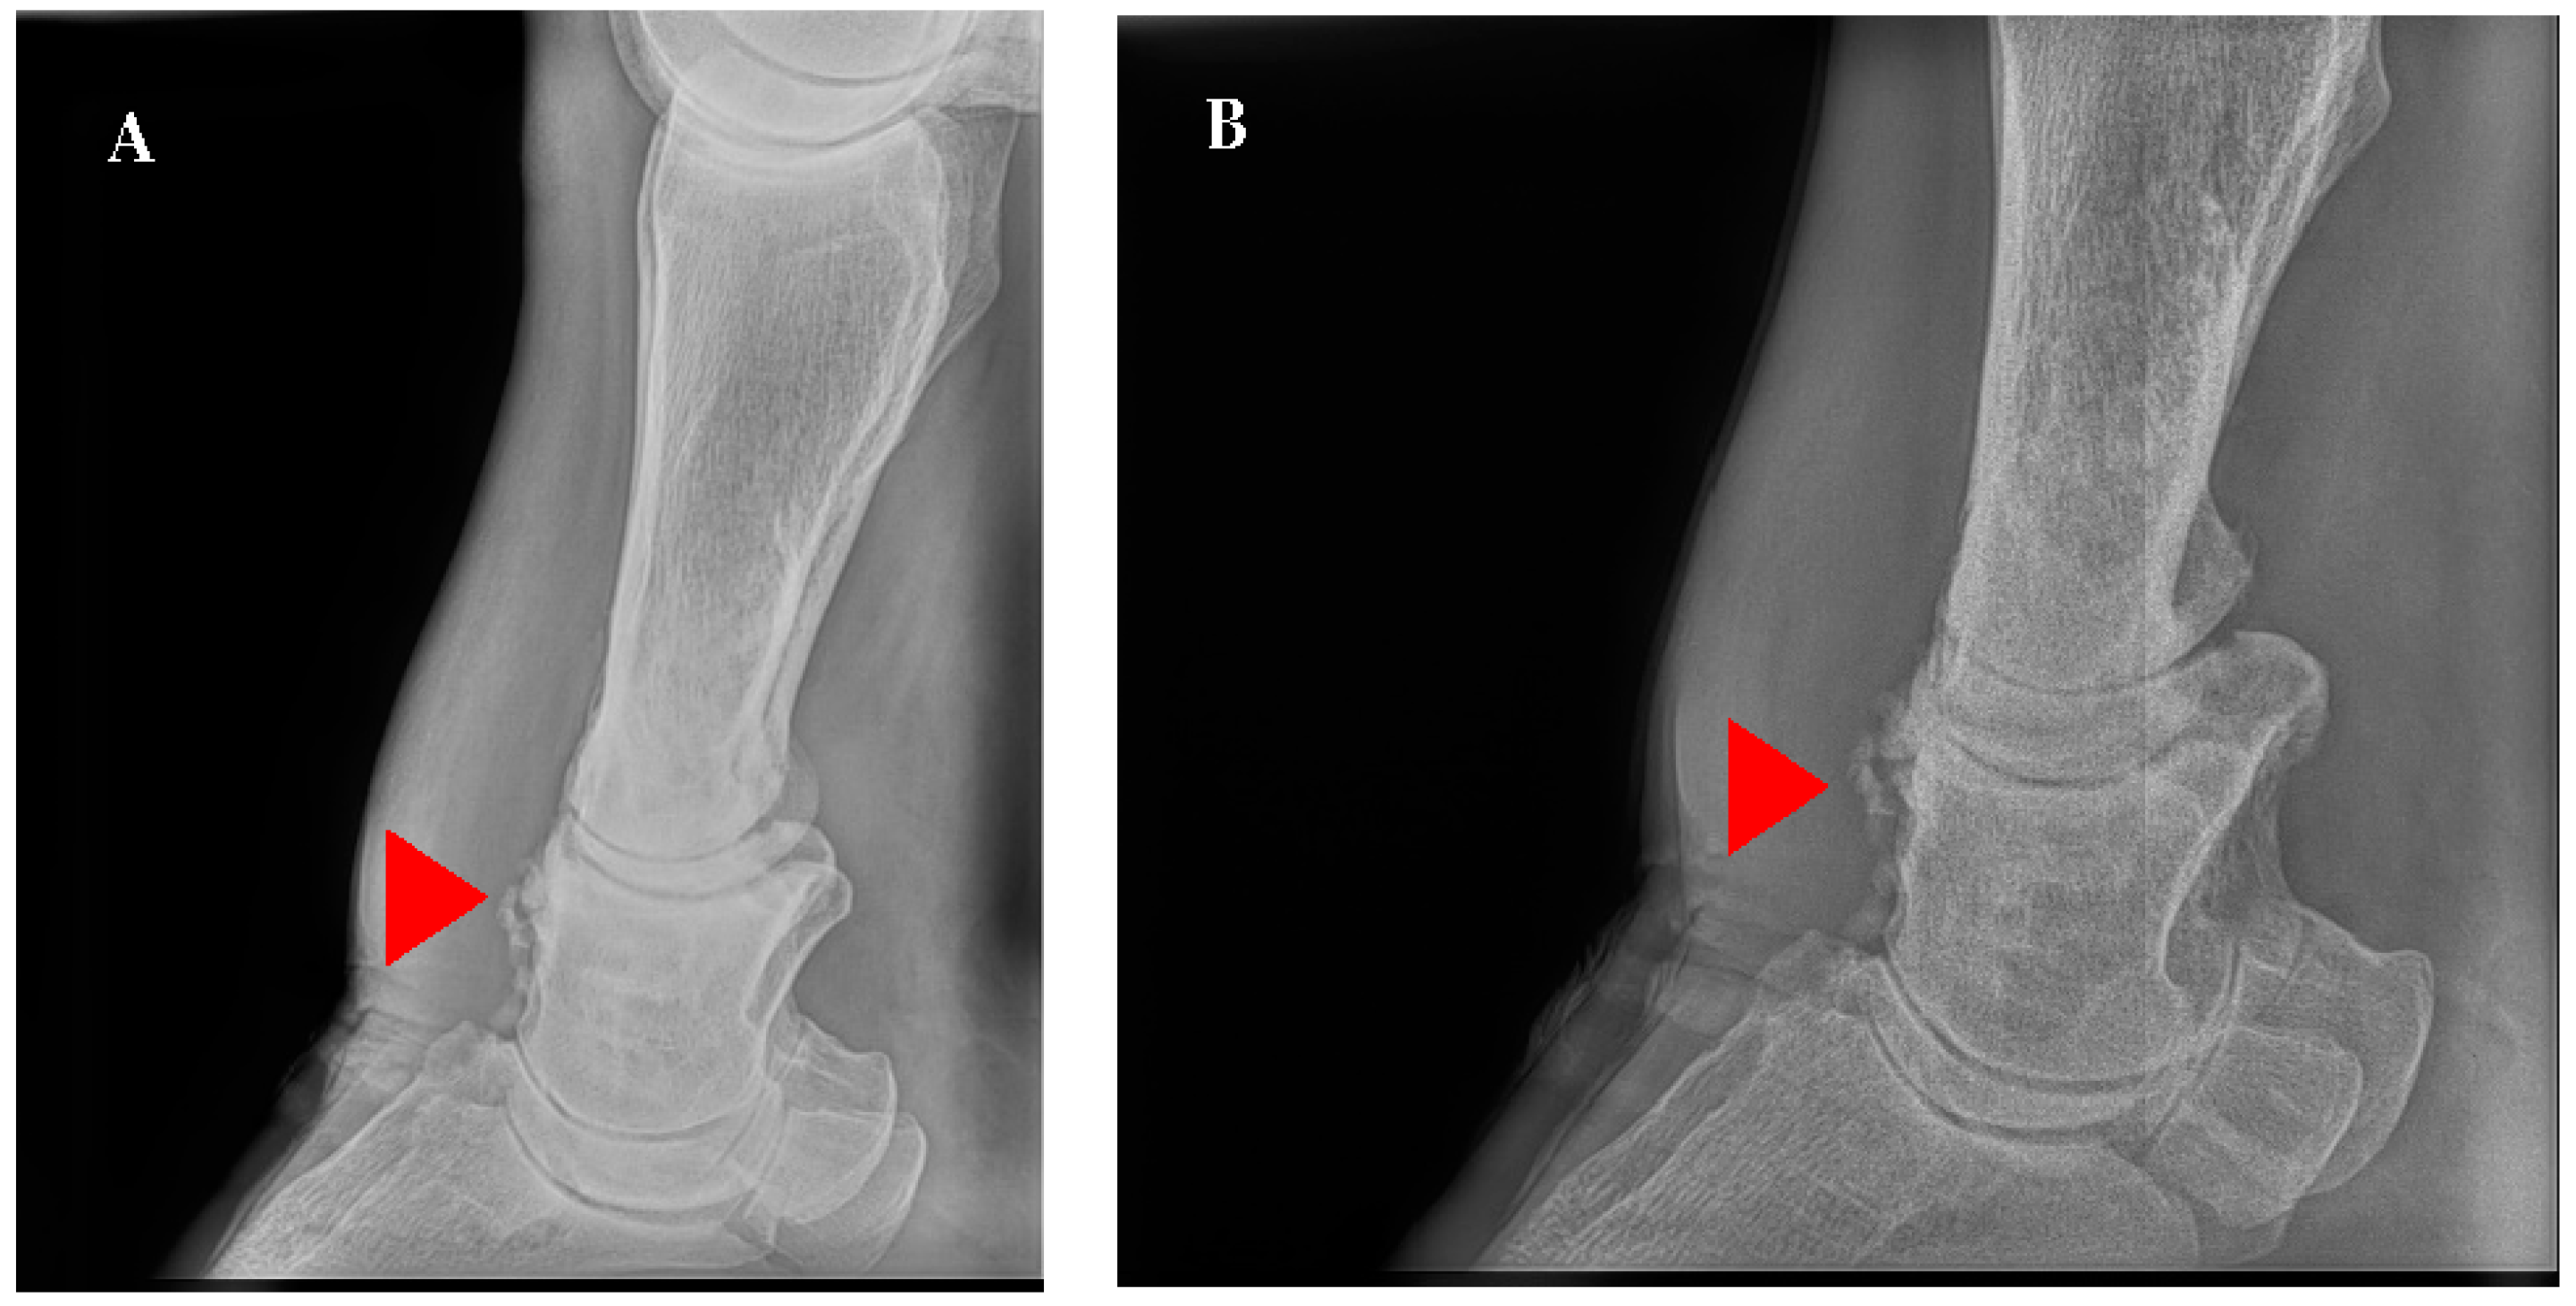

5.2. Diagnosis

6. Discussion